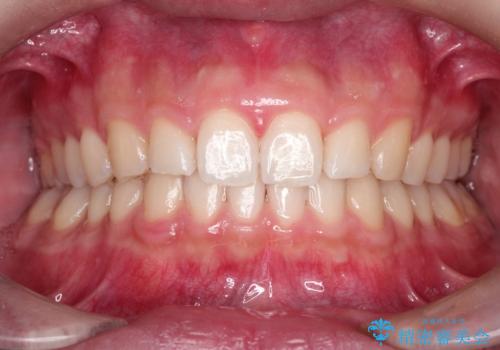

長い間コンプレックスだった前歯のすき間! 短期間終了。部分矯正症例 (インビザライン矯正)